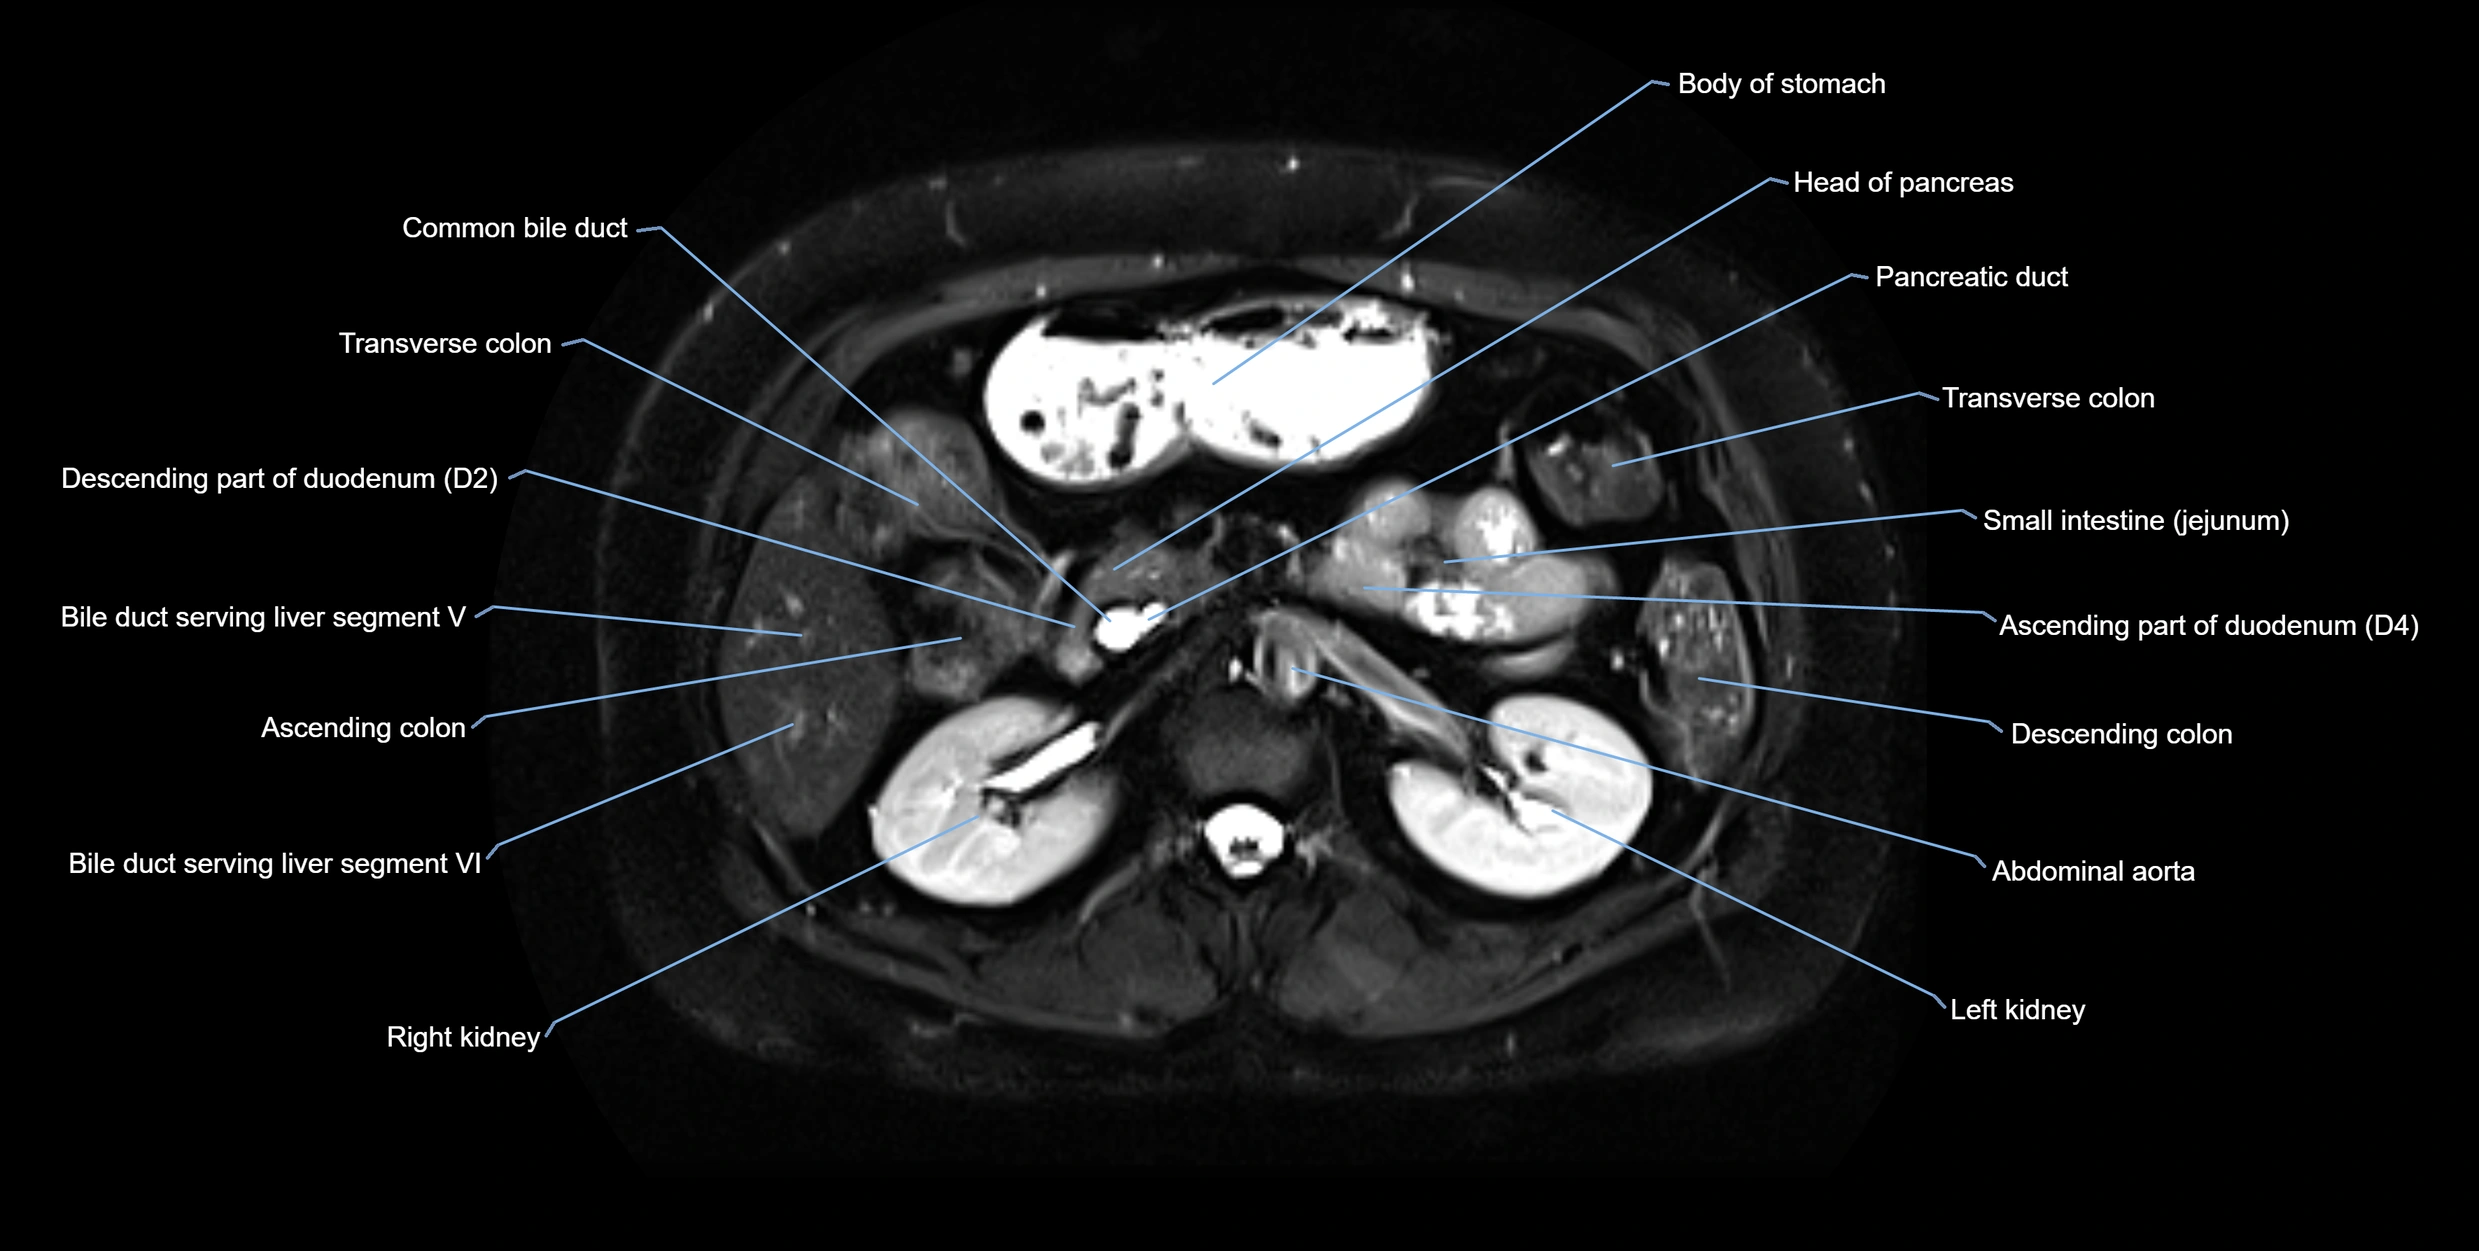

MRI image

image